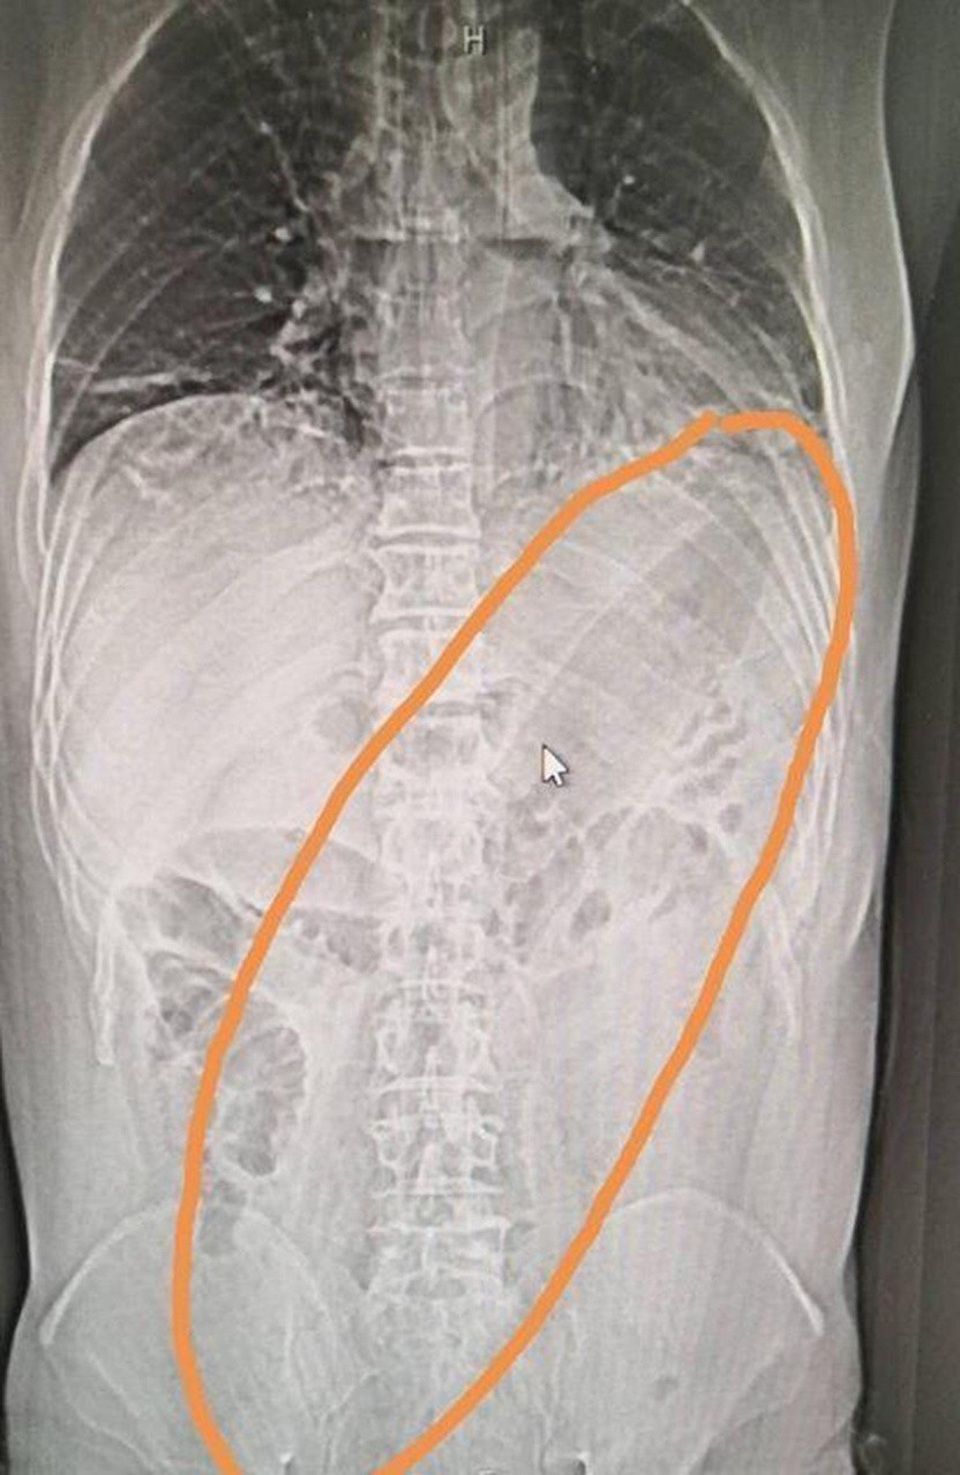

Hình ảnh chụp X quang cho thấy quả cà tím nằm nguyên vẹn trong ruột của bệnh nhân và anh ta phải trải qua phẫu thuật để lấy nó ra. Báo Kan Kan còn cho biết bệnh nhân đã nghĩ rằng trái cây mà cụ thể là quả cà có thể giúp mình trị chứng táo bón.

Đáng tiếc là quả cà tím mặc dù đúng là có tác dụng thanh nhiệt, giải độc, nhuận tràng nhưng lại không thể phát huy hiệu quả khi còn nguyên như vậy. Nó đã mắc kẹt ở một đoạn gấp khúc, khiến người đàn ông bị sưng dạ dày và viêm phổi. May mắn là hiện tại, sau khi tiến hành phẫu thuật, bệnh nhân đang dần dần hồi phục.